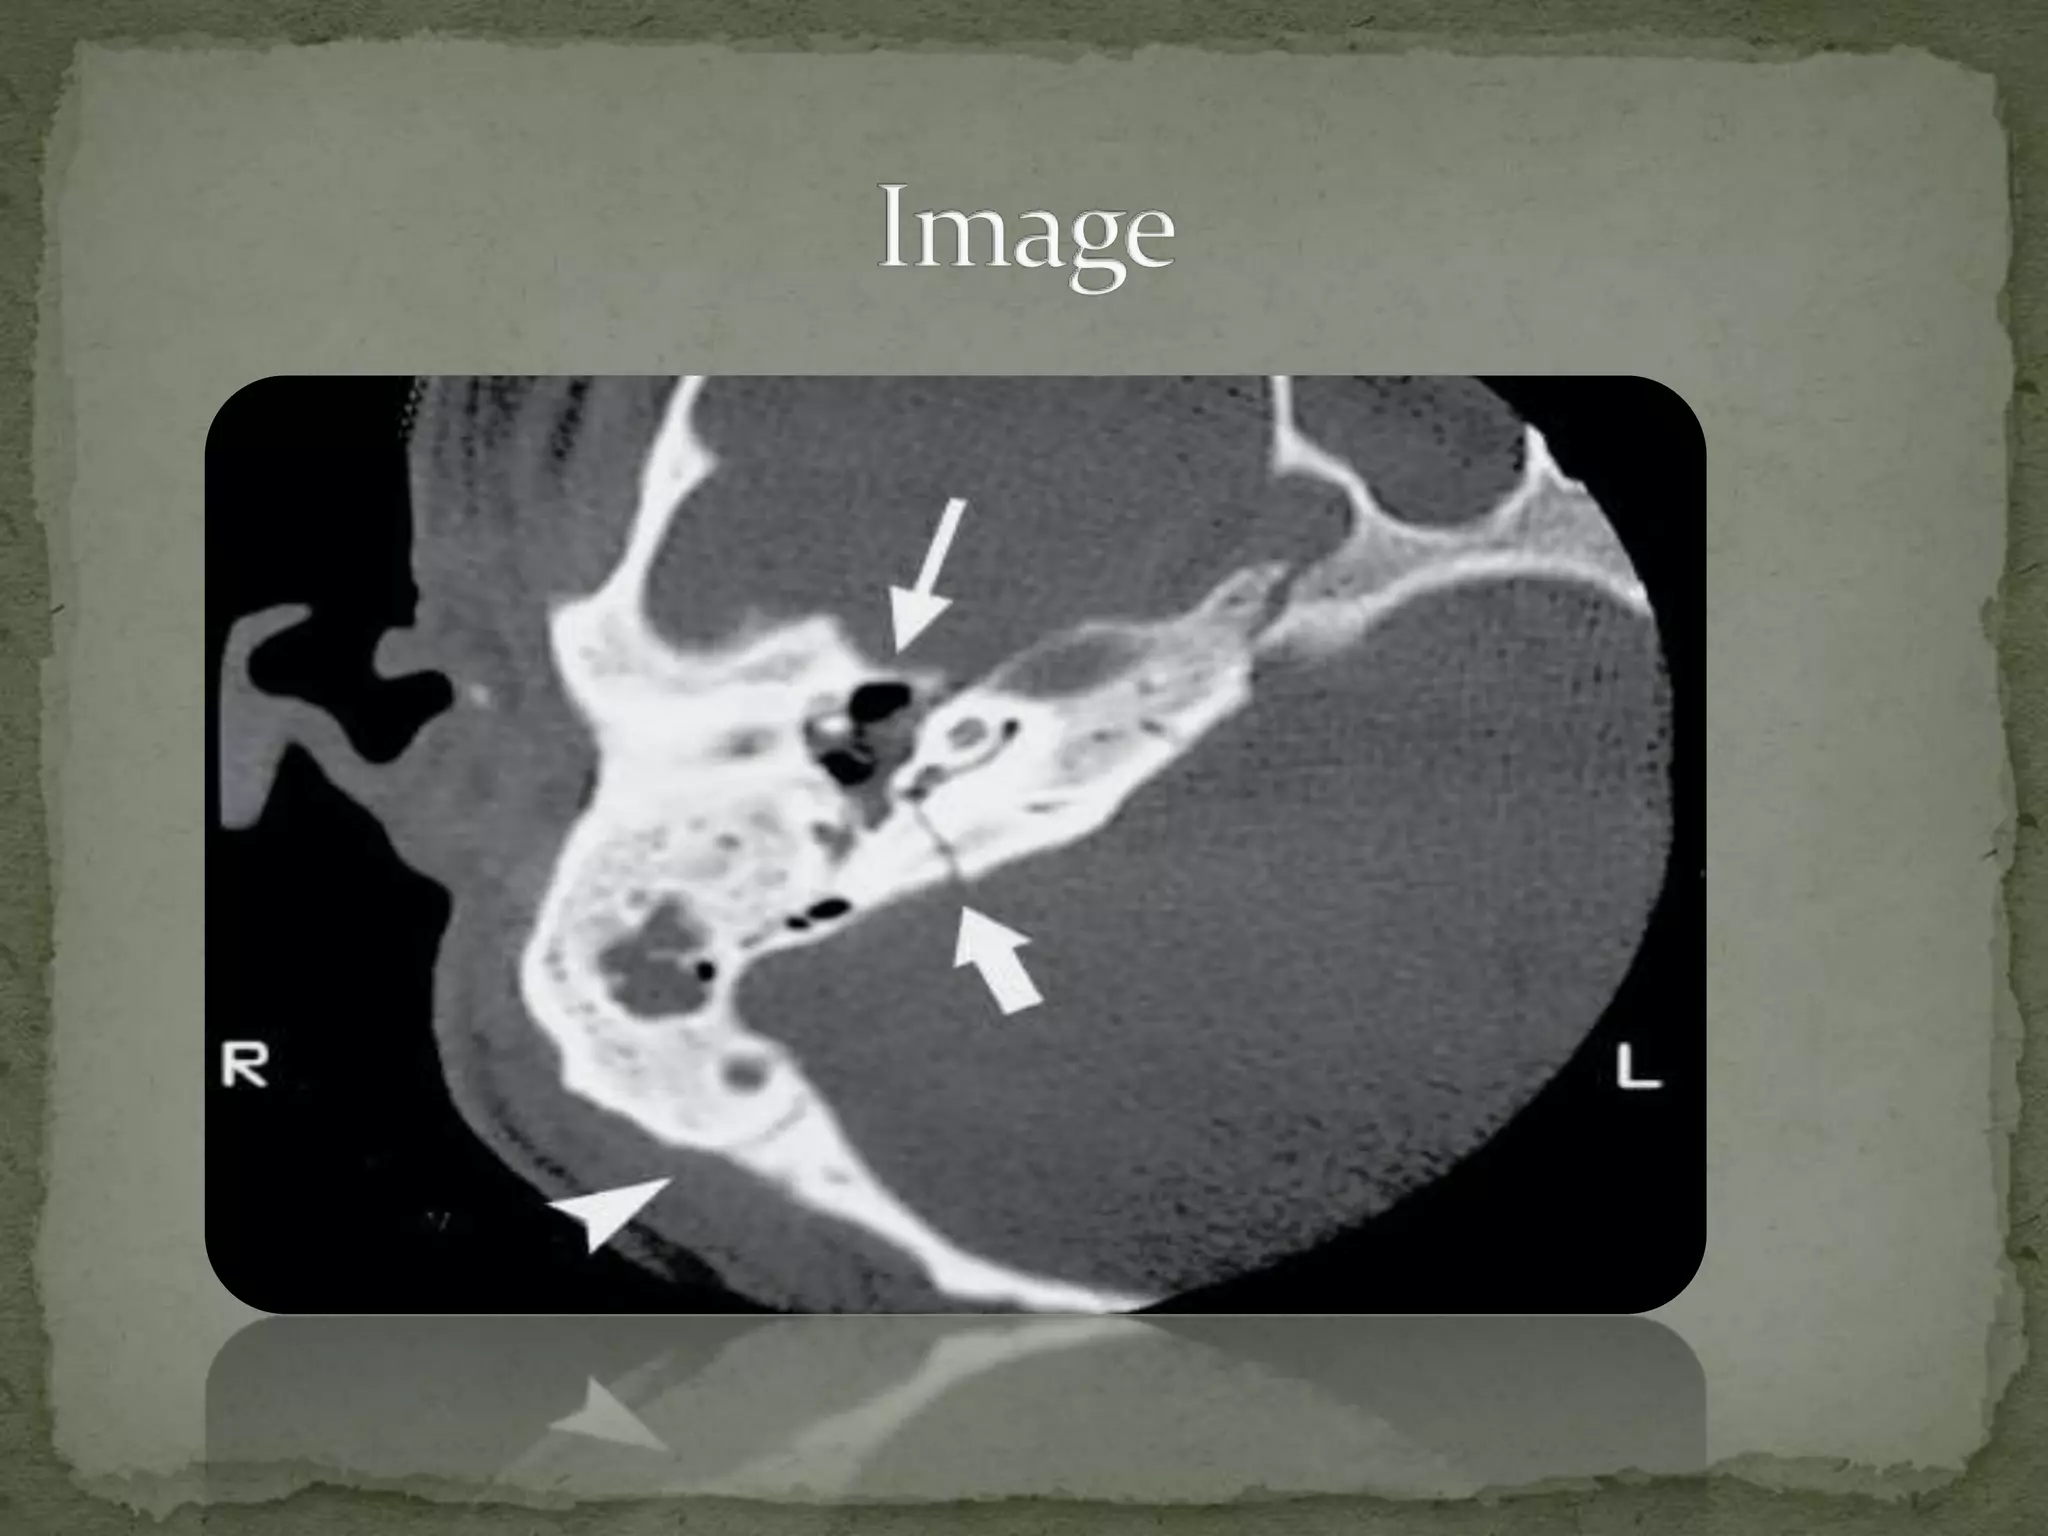

Initial noncontrasted CT brain, showing the basilar skull fracture Basilar Skull Fracture Reddit a fracture of this part of the skull is a basilar skull fracture. The areas around the eyes, ears, nose, or at the top of the neck, near the spine. 86k subscribers in the emergencymedicine community. Roughly, you can divide the skull into the calvaria or skull cap (this is. — this broke his skull at the. Basilar Skull Fracture Reddit.